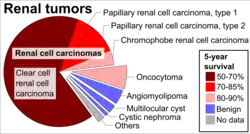

Renal oncocytoma is thought to arise from the intercalated cells of collecting ducts of the kidney. It represent 5% to 15% of surgically resected renal neoplasms. Ultrastructurally, the eosinophilic cells have numerous mitochondria.

Renal oncocytoma is considered benign, cured by nephrectomy. There are some familial cases in which these tumors are multicentric rather than solitary.[4] However, they may be resected to exclude a malignant tumor, e.g. renal cell carcinoma.

Prognosis

The overall five-year survival rate has been estimated to be 63%, with 100% disease-specific survival.[5]